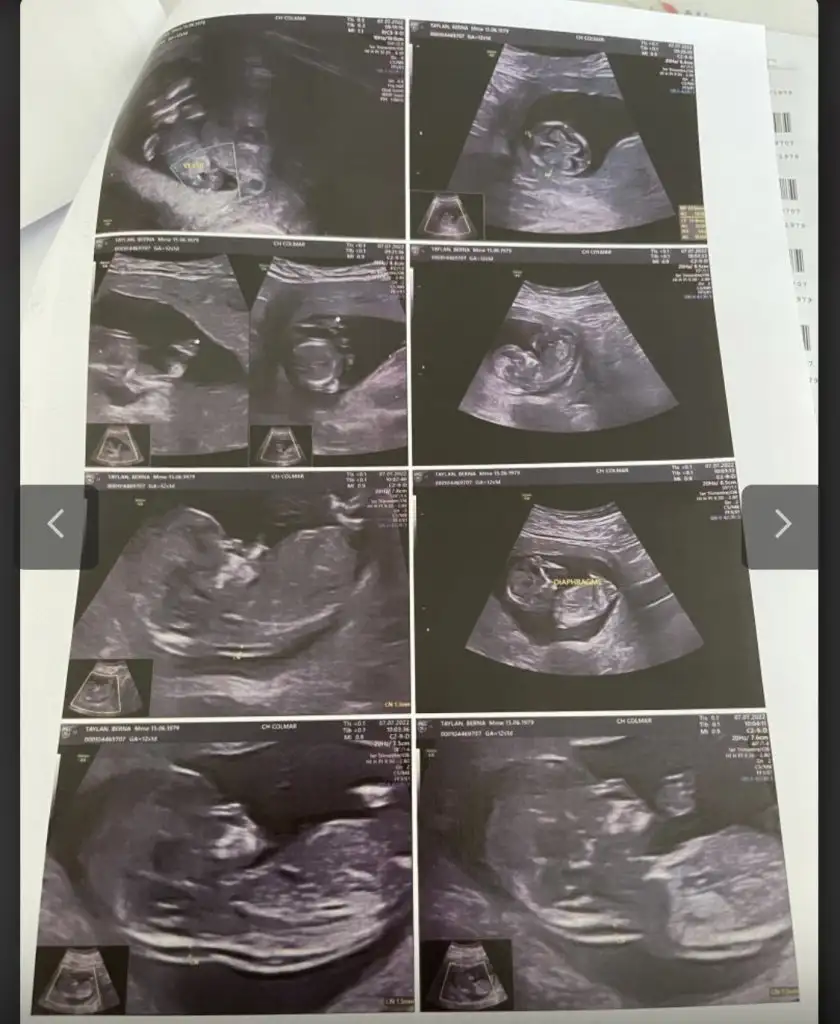

Cinsiyet tahmini

• 3D14E57E-7BD9-4704-BCF4-2E7C33FBDF9C.webp

3D14E57E-7BD9-4704-BCF4-2E7C33FBDF9C.webp

40,4 KB · Görüntüleme: 41